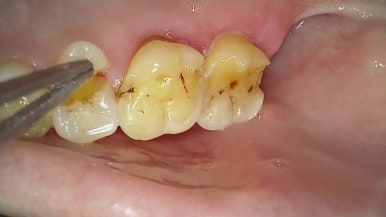

한 환자분은 단단한 음식을 씹다 오른쪽 위 어금니 통증으로 내원하셨습니다.

엑스레이상 특이사항은 없었지만,

구강 내 검사 결과 치아가 반으로 쪼개진 상태였습니다.